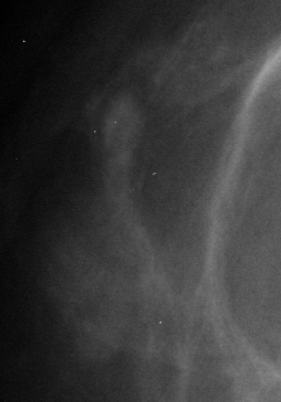

In our experiments, we use the Digital Database for Screening Mammography (DDSM) [4], a collaboratively maintained public dataset at the University of South Florida. It comprises approximately 2500 studies each containing both mediolateral oblique (MLO) and craniocaudal (CC) views of each breast. Each image is grayscale and accompanied by a mask specifying the region of the pre-segmented mass if present. Examples of benign and malignant masses are shown in Fig. 1.